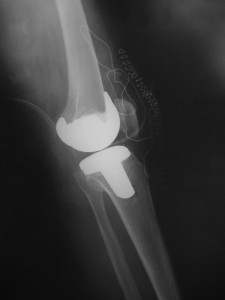

Total Diz Protezi

Total Diz Protezi ameliyatı 50 yılı aşkın bir süredir tüm dünya üzerinde bir çok farklı merkezde başarı ile uygulanmaktadır. Daha önceki yıllarda bu protezlerin ömürleri 10-15 yıl olarak bilinmekteyken, artık gelişen implant teknolojisi, artan bilgi paylaşımı ve ameliyat teknikleri ile bu yıl çok daha üst seviyelere çekilmiştir.

Total Diz Protez ameliyatı kliniğimizde endikasyon dahiline her yaşa başarı ile uygulanmaktadır. Örnek olgumuz: